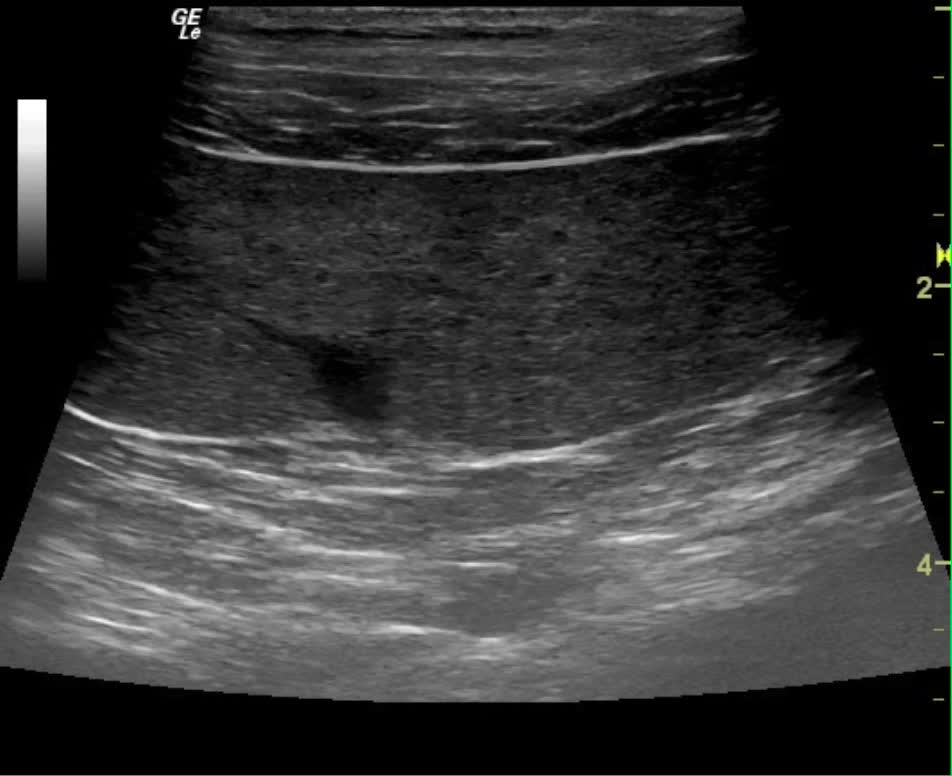

From members.sonopath.com

Lymphoma in a 4 year old FS Labrador Retriever mix dog Members Labrador Retriever Lymphoma Learn more about symptoms, stages, and treatments of canine lymphoma. Enlarged lymph nodes may also occur due to infections or autoimmune diseases, so your veterinarian will perform tests to determine the. Lymphosarcoma is a common cancer of lymphocytes in dogs and can occur in. Learn about the signs of lymphoma in dogs, the stages, treatments, and possible life expectancy of. Labrador Retriever Lymphoma.

Lymphoma in a 4 year old FS Labrador Retriever mix dog Members Labrador Retriever Lymphoma Lymphosarcoma is a common cancer of lymphocytes in dogs and can occur in. Not all dogs with enlarged lymph nodes have lymphoma. Enlarged lymph nodes may also occur due to infections or autoimmune diseases, so your veterinarian will perform tests to determine the. Dog lymphoma is cancer affecting white blood cells. Learn about the signs of lymphoma in dogs, the. Labrador Retriever Lymphoma.

Lymphoma in a 4 year old FS Labrador Retriever mix dog Members Labrador Retriever Lymphoma Learn more about symptoms, stages, and treatments of canine lymphoma. Enlarged lymph nodes may also occur due to infections or autoimmune diseases, so your veterinarian will perform tests to determine the. One of the most common instances of dog cancer is lymphoma. Not all dogs with enlarged lymph nodes have lymphoma. Lymphosarcoma is a common cancer of lymphocytes in dogs. Labrador Retriever Lymphoma.

Lymphoma in a 4 year old FS Labrador Retriever mix dog Members Labrador Retriever Lymphoma One of the most common instances of dog cancer is lymphoma. Learn about the signs of lymphoma in dogs, the stages, treatments, and possible life expectancy of a dog with lymphoma. Lymphosarcoma is a common cancer of lymphocytes in dogs and can occur in. Not all dogs with enlarged lymph nodes have lymphoma. Dog lymphoma is cancer affecting white blood. Labrador Retriever Lymphoma.